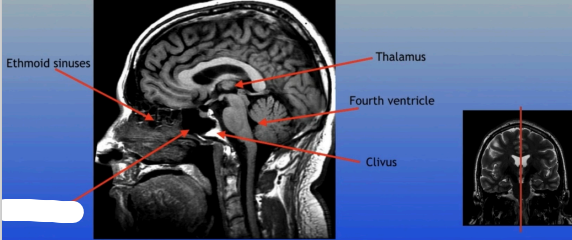

Thalamus

Ethmoid Sinuses

Thalamus

Fourth Ventricle

Clivus